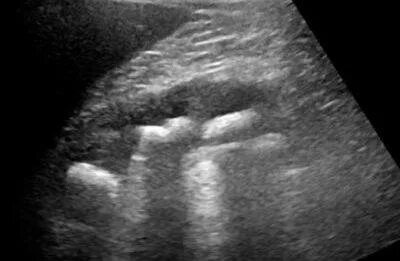

Симптом выделяющихся пирамид на узи. синдром гиперэхогенных пирамид на узи. синдром гиперэхогенных пирамид почек узи. медуллярная губчатая почка узи.

Синдром выделяющихся пирамид. гиперэхогенные пирамидки. симптом гиперэхогенных пирамидок. синдром гиперэхогенных пирамид почек.

Синдром выделяющихся пирамид. симптом выделенных пирамид. симптом выделяющихся пирамидок. синдром перимедуллярного кольца почки что это.